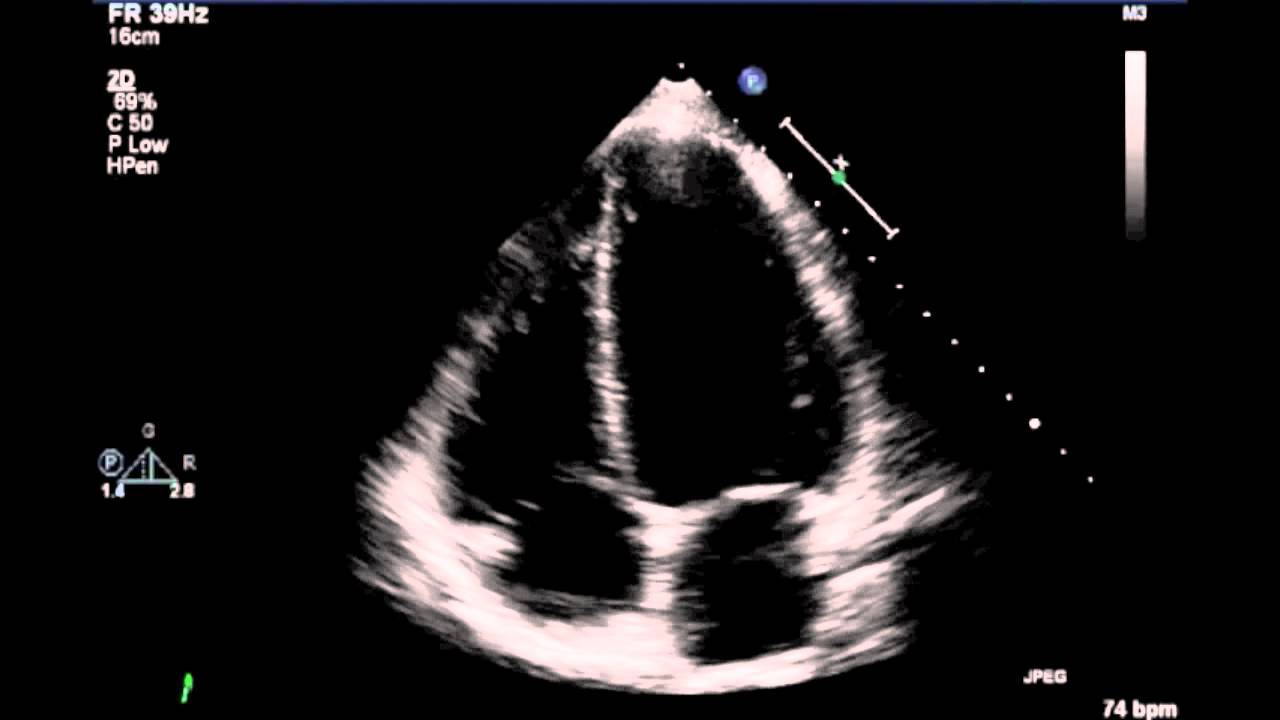

As I turn, I see my heart for the first time…

Watch it beat.

The heart is a violent place.

But now I am face to face with my heart…

And I see it for what it is…

A center of violent energy…

Just barely under control.